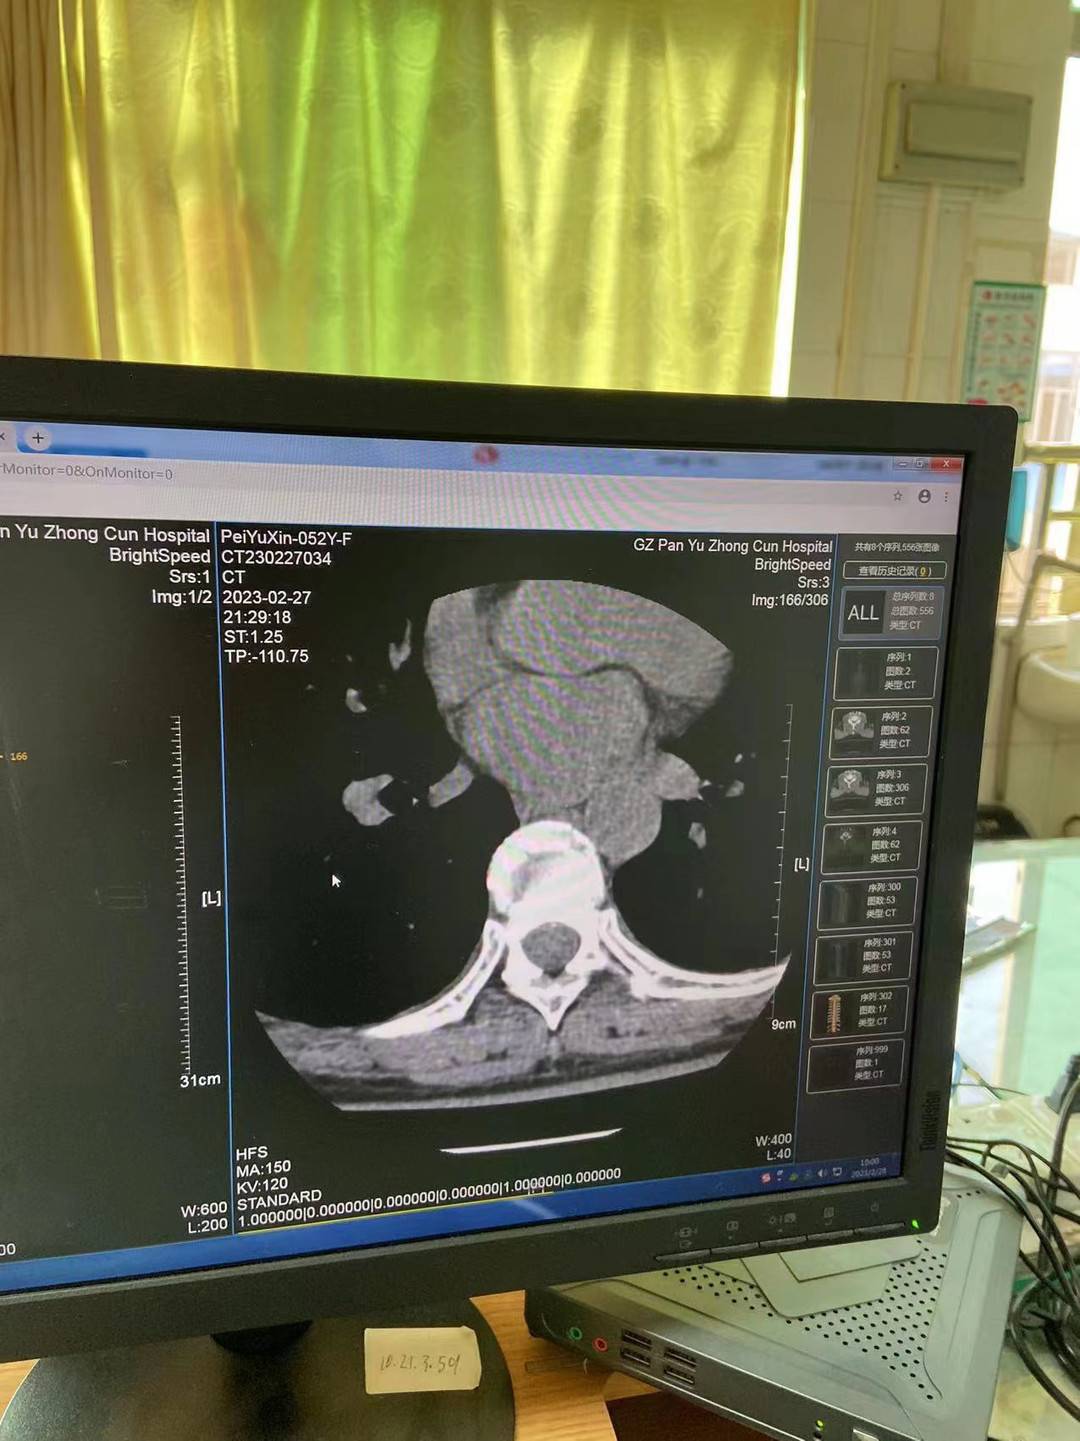

医院出示检查报告 图源受访者

裴谕新向记者提供的CT检查报告显示,胸8椎体明显变扁塌陷,压缩约1/3,骨碎片向周围移位,胸8锥体压缩性骨折。目前她仍然在医院接受治疗。